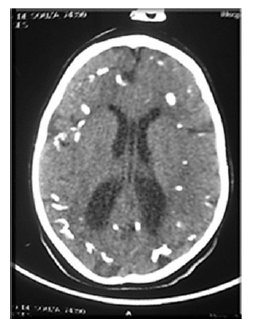

Recém-nascido de 5 dias de vida, do sexo masculino, nasceu de parto vaginal, com as seguintes características: IG = 36 semanas, PN = 2.380 g (AIG), Apgar 7/8, PC = 29 cm. A mãe não realizou pré-natal e apresenta o seguinte perfil: G3P2A1, 28 anos de idade, tabagista de 10 cigarros ao dia, nega consumo de álcool e de drogas ilícitas. O RN ficou internado desde o nascimento por sepse precoce. Após três dias de vida, seu caso evoluiu para crise convulsiva. Realizou tomografia de crânio, apresentada na imagem.

A respeito desse caso clínico e de aspectos a ele relacionados, julgue os itens a seguir.

O CMV é um importante causador de infecção congênita, um dos prováveis diagnósticos do caso apresentado. É um herpes vírus com tropismo pelo SNC. É excretado no sangue, na urina, no leite, na saliva, no sêmen e na secreção do colo uterino. Os RN podem ser assintomáticos, apresentando alterações tardias (surdez e deficits neurológicos).